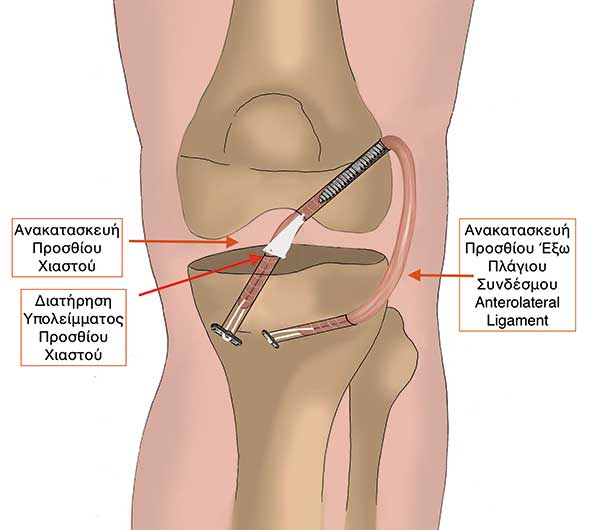

Προτείνουµε στον ασθενή µια ολοκληρωµένη θεραπεία (Εικόνες 3 & 4):

Συνδεσµοπλαστική προσθίου χιαστού

Συνδεσµοπλαστική του προσθίου έξω πλάγιου συνδέσµου (anterolateral ligament) και

Πλήρης διατήρηση του υπολείµµατος του προσθίου χιαστού µε σκοπό την πλήρη επαναφορά του γόνατος στη φυσιολογική του κατάσταση.